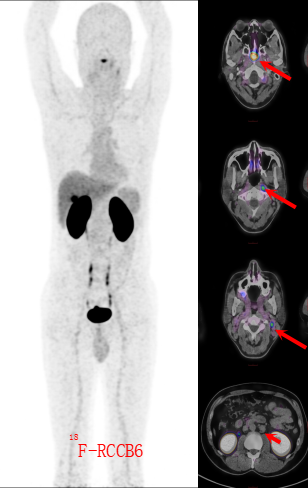

患者入住江西省肿瘤医院鼻咽癌二病区后,先后接受了18F-FDG与18F-CD70双探针PET/CT扫描。

FDG图像上(图1),鼻咽部软组织肿块伴高代谢,同时双颈、腹膜后淋巴结“繁星样”高亮——似乎都在指向“晚期鼻咽癌并广泛转移”。 然而,CD70探针却“语出惊人”:鼻咽病灶浓聚,却有一部分淋巴结仅轻度摄取,甚至阴性(图2)! 核医学科立即发出提示:“双原发可能,建议病理再分型。”

图二